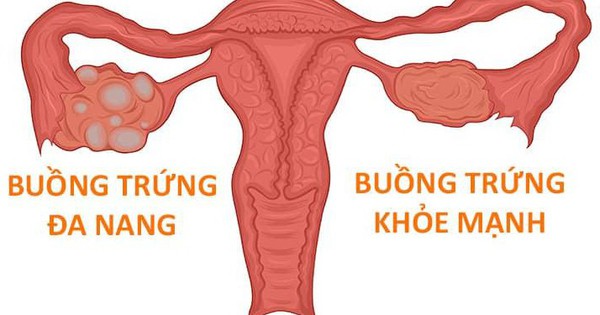

Hội chứng buồng trứng đa nang ảnh hưởng đến khoảng 6 – 12% phụ nữ trong độ tuổi sinh sản.

Tại Việt Nam, con số này đang có xu hướng gia tăng do lối sống và chế độ dinh dưỡng. Đặc trưng của hội chứng buồng trứng đa nang là tình trạng cơ thể sản sinh quá mức nội tiết tố nam (androgen) và insulin, làm gián đoạn quá trình rụng trứng tự nhiên.